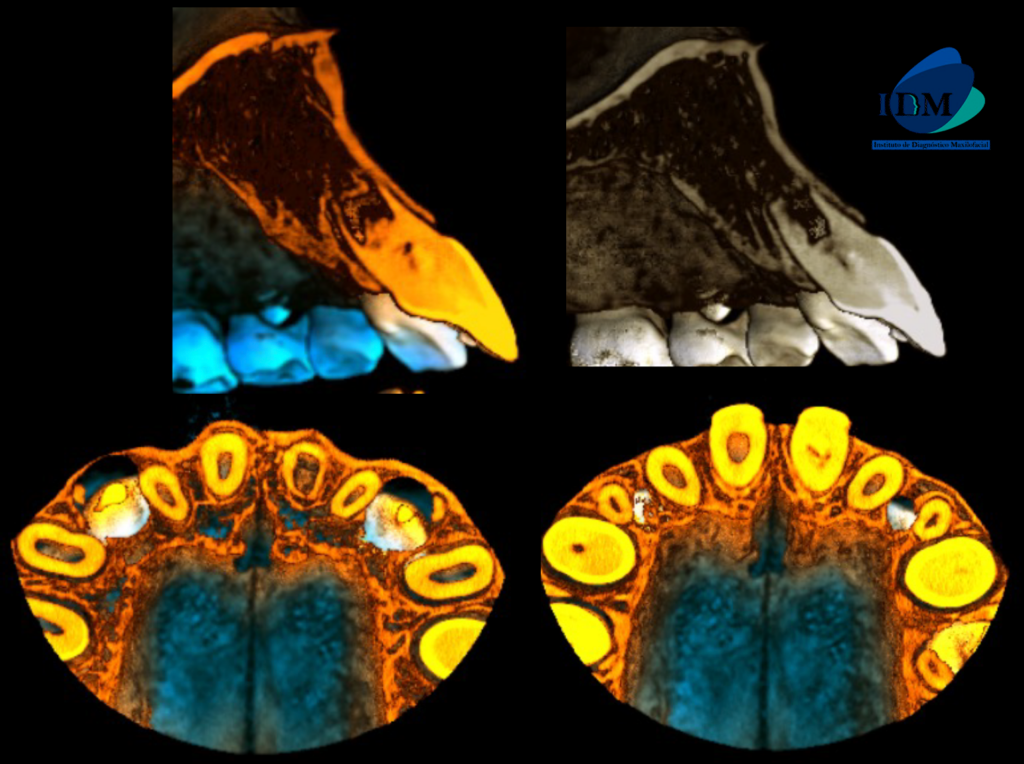

A la evaluación de la tomografía volumétrica (cone beam) de campo reducido en los cortes axiales (Figura 2) y transaxiales (Figura 3) se observa la pieza 21 con material restaurador coronal, obliteración de cámara y conducto radicular en tercio cervical y medio; además de observar la formación radicular incompleta caracterizado por tercio apical de conducto y foramen apical amplio; signos compatibles con secuela de trauma dental.

CORTES AXIALES

CORTES TRANSAXIALES

En la reconstrucción 3D se representa la obliteración del conducto y foramen apical amplio de la pieza 21 (Figura 4)

RECONSTRUCCIÓN 3D